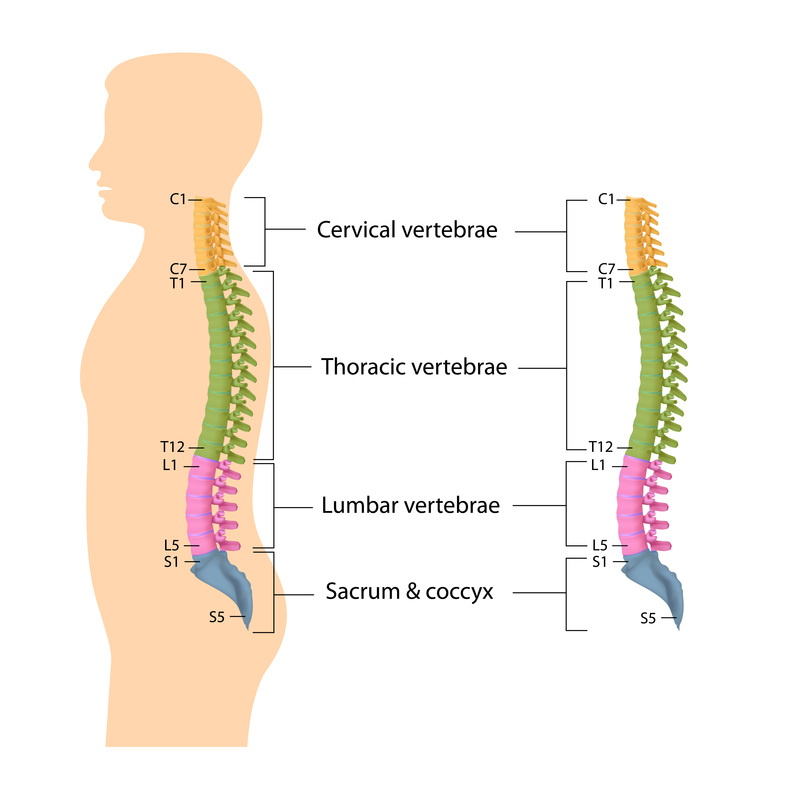

silikonsheet.blogg.se – Spine diagram

Bones-of-the-Spine-for-EMS – Handley Law

human spine anatomy diagram

Diagram Human Spine Name Description All Sections Vertebrae Vector …

Thoracic spine anatomy, function & thoracic spine injury